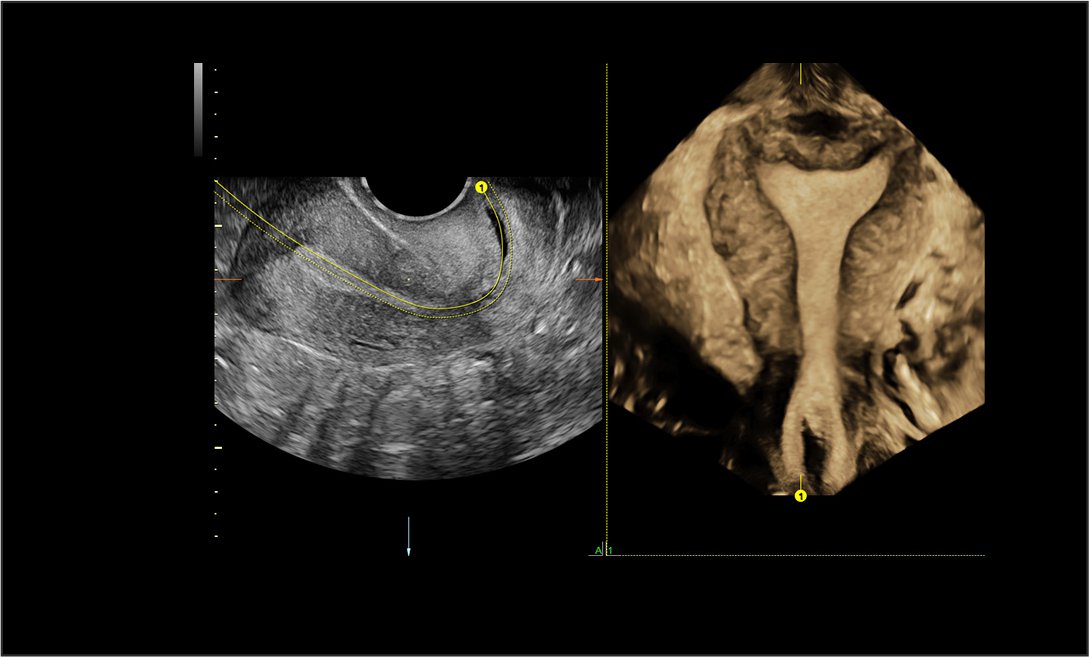

A transvaginal ultrasound may be done to produce a clearer image. This ultrasound is more likely to be used during the early stages of pregnancy, when capturing a clear image may be more difficult. For this test, a small ultrasound probe is inserted into the vagina. The probe rests against the back of your vagina while the images are captured.

Unlike a traditional 2-D ultrasound, a 3-D ultrasound allows your doctor to see the width, height, and depth of the fetus and your organs. This ultrasound can be especially helpful in diagnosing any suspected problems during your pregnancy.

A 3-D ultrasound follows the same procedure as a standard ultrasound, but it uses a special probe and software to create the 3-D image. It also requires special training for the technician, so it may not be as widely available.